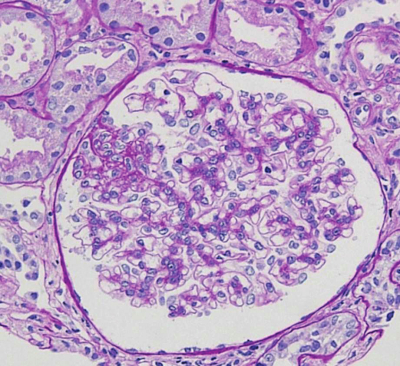

尿所見:蛋白3+、潜血1+、沈渣に赤血球5~10/1視野、顆粒円柱1個/数視野、卵円形脂肪体1~4/1視野、尿蛋白4.8g/日。血液生化学所見:総蛋白4.5g/dL、アルブミン1.8g/dL、IgG 547mg/dL (基準960~1,960)、IgA 250mg/dL(基準110~410)、IgM 67mg/dL(基準65~350)、尿素窒素20mg/dL、クレアチニン1.1mg/dL、トリグリセリド240mg/dL、LDLコレステロール220mg/dL。ASO 180単位(基準250以下)。腎生検のPAS染色標本を別に示す。